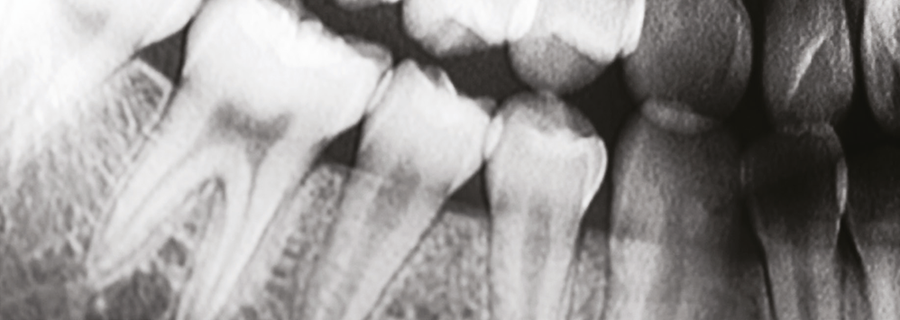

-用于牙齿和颌/头成像的基于CsI的高分辨率X射线检测

使用碘化铯X射线闪烁体CsI X-ray Scintillators解决方案的关键优点是低x射线剂量、ZD分辨率和增强的图像质量。Scintacor基于组件技术方面的丰富经验,创造了一系列定制的牙科碘化铯(CsI)闪烁体。

使用光导微柱状CsI作为Scintacor口腔内设备的闪烁层,结合x光阻挡光纤面板(FOP),产生了一个极高分辨率的x光传感器,用于连接到您的电荷耦合器件或互补金属氧化物半导体传感器。fop可以定制各种尺寸、厚度和材料,CsI层的厚度也可以调整,以有利于更好的信噪比或分辨率,或者在两者之间取得平衡。通过改变反射器的颜色,可以进一步定制性能。

在Scintacor的口外设备中,使用更厚的光导微柱状CsI作为闪烁层,结合高纵横比的x光阻挡纤维光学面板(FOPs),产生了异常明亮和高分辨率的x光传感器。这种设备非常适合连接到基于电荷耦合器件或互补金属氧化物半导体的传感器或传感器阵列,用于颌或头扫描应用。fop可以定制各种尺寸、厚度和材料,CsI层厚度和反射器颜色也可以调整,以实现信噪比和分辨率之间的ZJ平衡。 颌部和头部x光扫描是动态应用,得益于使用Scintacor的低余辉CsI来限制运动模糊。